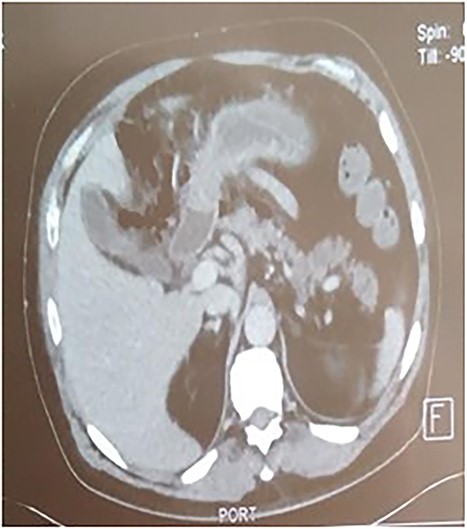

A 53-year-old man with no known medical history was admitted to the hospital because of epigastric pain persisting for 24 h, accompanied by weakness. Physical examination revealed a temperature of 39°C, severe dehydration, poor peripheral perfusion, a pulse of 110 bpm, blood pressure at 10/6 mm/Hg, a painful and tympanic abdomen without peristalsis, with tenderness over the epigastric region. Laboratory tests showed a lipase level of 667 U/l, sodium at 140 mmol/l, potassium at 4.5 mmol/l, creatinine at 106 μmol/l, urea at 6.5 mmol/l, alanine aminotransferase at 161 U/l, aspartate aminotransferase at 85 U/l, an elevated leukocyte count at 29,3 × 109/l. Abdominal CT with contrast revealed pancreatic necrosis with gas surrounding the pancreas, as well as pneumoperitoneum and in the right anterior pararenal space. Thickening of the mesentery root with lymph node enlargement (Figs 1–3).